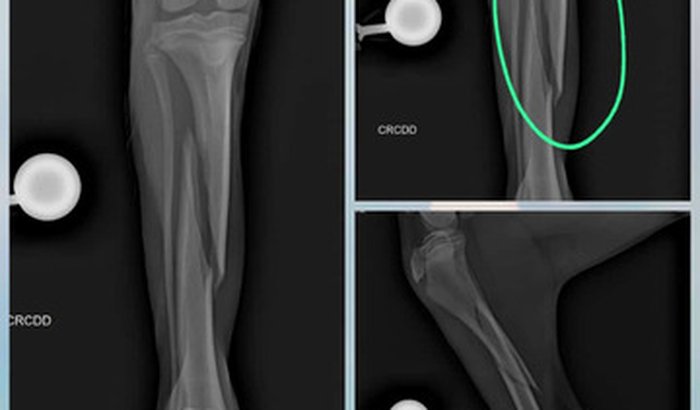

Boa noite gerente passando aqui pra pedir a ajuda de vcs meu dog quebrou a perninha e precisa com urgência fazer uma cirurgia ele ainda e filhote tem 7 meses e um macho se chama Apollo no momento não temos condições de custear a cirurgia